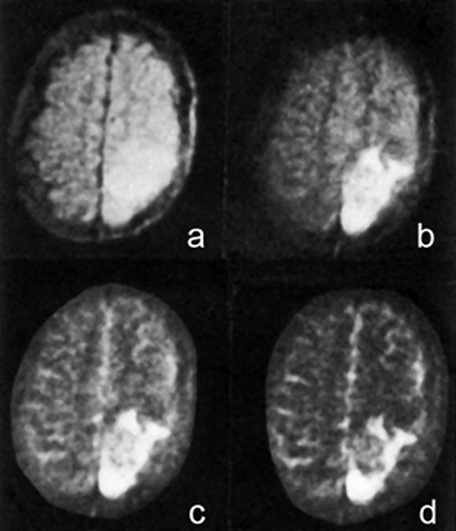

Figura 20-43:

Imágenes de espín-eco de 1984 de un tumor cerebral recurrente tomadas en un sistema de 0,14 Tesla; TEs (a-d) entre 20 y 300 ms.

Las imágenes se realizaron cinco años antes de la introducción de los agentes de contraste basados en Gd; el tumor se puede delinear mejor en la imagen (d) con un TE de 300 ms.

Ilustración de: Rinck PA, Bydder GM, y Harms SE. Imaginería por resonancia magnética del cerebro. Publicado en la primera edición de este libro de texto en 1985.